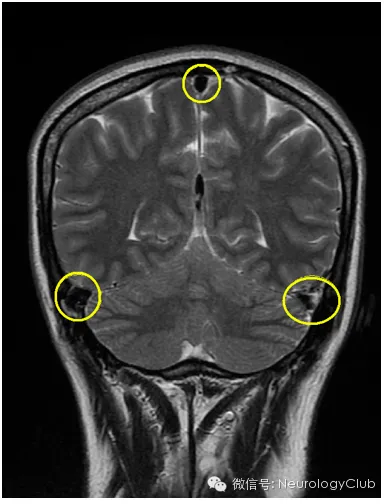

硬膜下积液表现为双侧对称性薄层积液,无占位效应,对下面的脑沟脑裂无压迫效应。

增强扫描时硬脑膜弥漫性增强增厚是颅内低压综合征的最具特征性表现,也是阳性率最高、出现最早的MRI表现。呈不间断的线样增强,无局限性结节,同时经常伴有硬脑膜增厚和皮层静脉的扩张,但从不累及软脑膜。

(3)静脉结构充盈(Engorgement of venous structures)

(4)垂体充血(Pituitary hyperemia)

(5)脑组织下沉(Sagging of the brain)